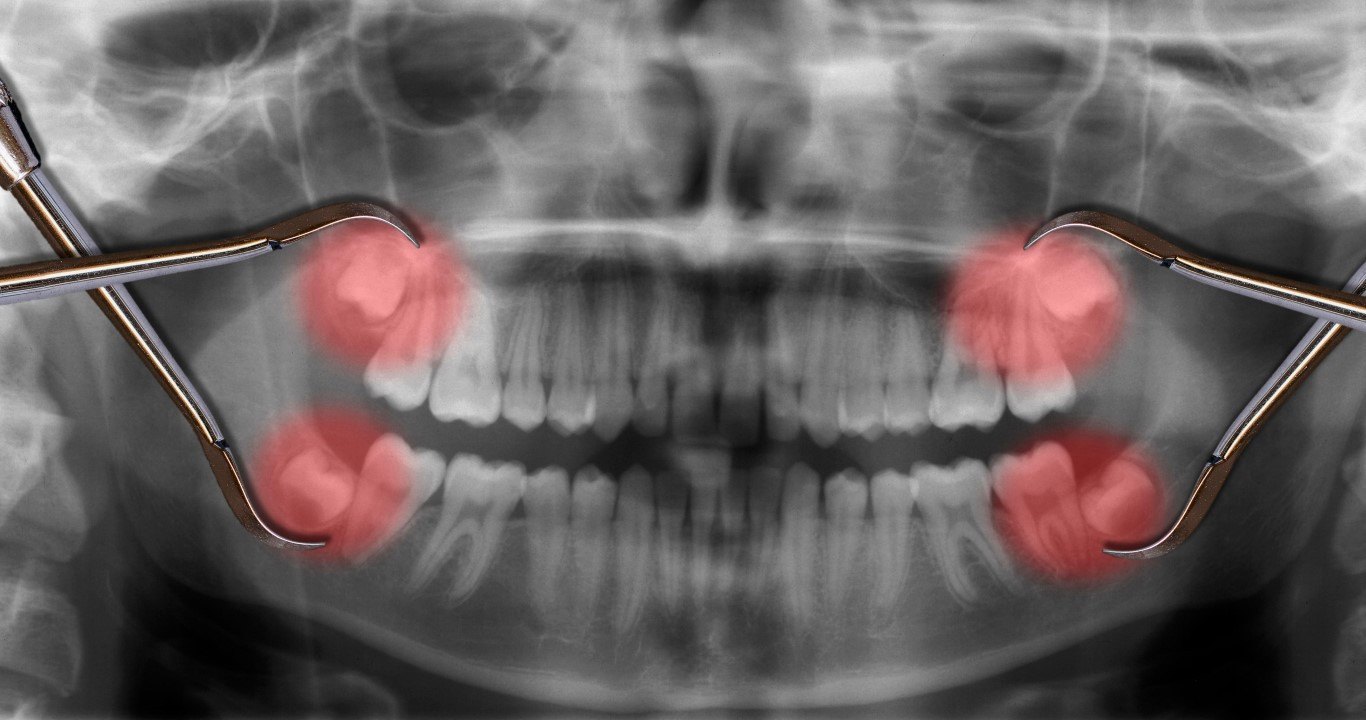

Yirmi yaş dişleri, çenenin iki tarafında en sonda bulunan üçüncü büyük azı dişlerine denir. Genellikle 16 ila 20 yaş arasında çıktığı için bunlara akıl dişi de denir. En son çıkan kalıcı dişler olduğu için, ağzınızda yirmilik dişler için yeterli boşluk olmayabilir. Bu da yirmi yaş dişlerinin dişeti dokusunun veya kemiğin altında veya başka bir dişin yanında gömülü kalmasına yol açabilir.

Diş Hekimi Dr. Onur Öztürk, yirmi yaş dişlerinin çene kemiğinin en arkasında yer alan dişler olduğunu ancak çeşitli nedenlerle bu dişlerin normal çıkışlarını tamamlayamadıklarını ifade etti:

“Çene kemiğinde en arkada yer alan yirmi yaş dişleri çıkamadığı zaman adı üzerinde 'gömülü' kalıyor, bu durumda üstünde bir miktar kemik engeli de olunca, buradan serbestleştirerek alınması gereken yirmilik dişler çoğunlukla operasyon ile çekilebiliyor.”

Öztürk, yirmi yaş dişlerimizin, atalarımız bugünkü gibi işlenmiş gıdalarla beslenmediklerinden dolayı, çiğ et ve sebzeleri parçalayabilmek için kafatasımızda yer etmiş olan çiğneyici dişler olduğunu, günümüzdeki modern beslenme modelinde bu dişlerin normal bir çene fonksiyonu için gerekliliğinin kalmadığını belirtti. Bununla beraber Öztürk, küçülen kafatasında yer bulmakta zorlanan yirmi yaş dişlerinin gömülü kalabileceğini ya da çıkmak için yer bulamayınca enfeksiyon gibi sorunlara yol açabileceğini ve şiddetli ağrılara neden olabileceğini söyledi.